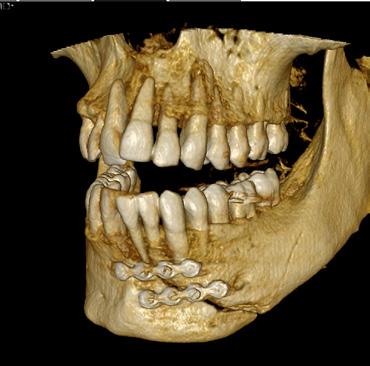

Simplify and expand your 3D diagnostics with the new ORTHOPANTOMOGRAPH™ OP 3D™ LX

Leading innovator of dental imaging technologies, DEXIS, has launched the next-generation OP 3D.

Built on OP 3D technology, the OP 3D LX imaging platform expands your 3D diagnostic capabilities with a wide range of clinical applications that support your evolving practice and enhance diagnostic confidence.

Consistent, high-quality images

Figure 4. Maxillofacial surgery. Figure 6. TMJ analysis. Figure 8. Airway analysis. Figure 10. Periodontics. Figure 5. Orthodontics. Figure 7. Implant placement. Figure 9. Prosthodontics. Figure 11. Endodontics.

Field of View

size (HxD)

Can be adjusted to offer up to 96 unique sizes

Clinical application

Localised diagnostics

Endodontic evaluation, single implant sites, and pathoses

Single arch

Implant planning, surgical guide creation, and impacted canines

Compact dual arch

Mandibular and maxillary treatment planning of dental implants in both arches

Complete dentition

Mandible and maxilla with 3rd molar region, and lower maxillary sinusesideal for multiple implants or periodontal evaluation

Entire dentition

Mandible and maxilla, bilateral TMJ, sinus, and pharyngeal airway

Maxillofacial complex

Mandible and maxilla, bilateral TMJ, upper and lower airway, soft tissue profile, OMS, and orthodontic analysis

landmarks, annotating mandibular nerve canals, tracing patientspecific panoramic curves for mandible and maxilla and merging CBCT and intraoral scan data for improved implant planning. These intuitive award-winning software features support a more efficient workflow allowing you to spend less time in the software and more time with your patient.